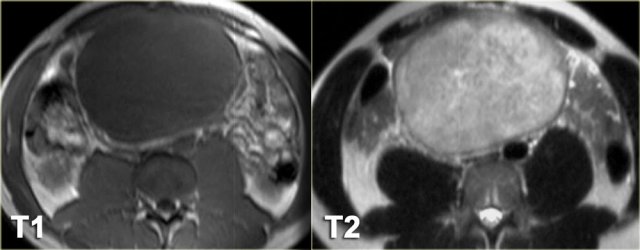

Peritoneal inclusion cyst (3)

On the left another example of a peritoneal inclusion cyst.

There is a nice correlation between the MR and the specimen.